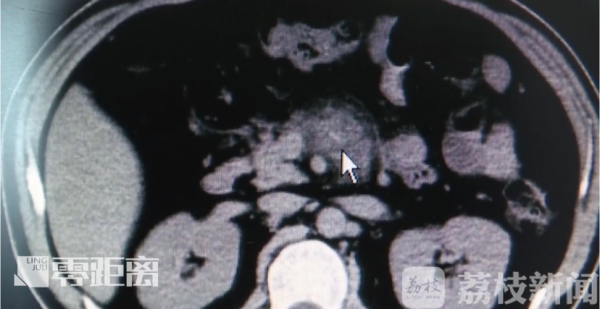

医生给他做了腹部CT才发现,有一根异物,从胃部后壁穿了出来。

很快,专家就对靳先生做了腹腔镜探查,并实施了手术。让人惊讶的是,罪魁祸首竟然是一根牙签。医生表示,本来牙签到了胃里可以取出来,但由于患者拖了很久才来医院,结果牙签一直到了肠子里,还戳破了肠子和胰腺。